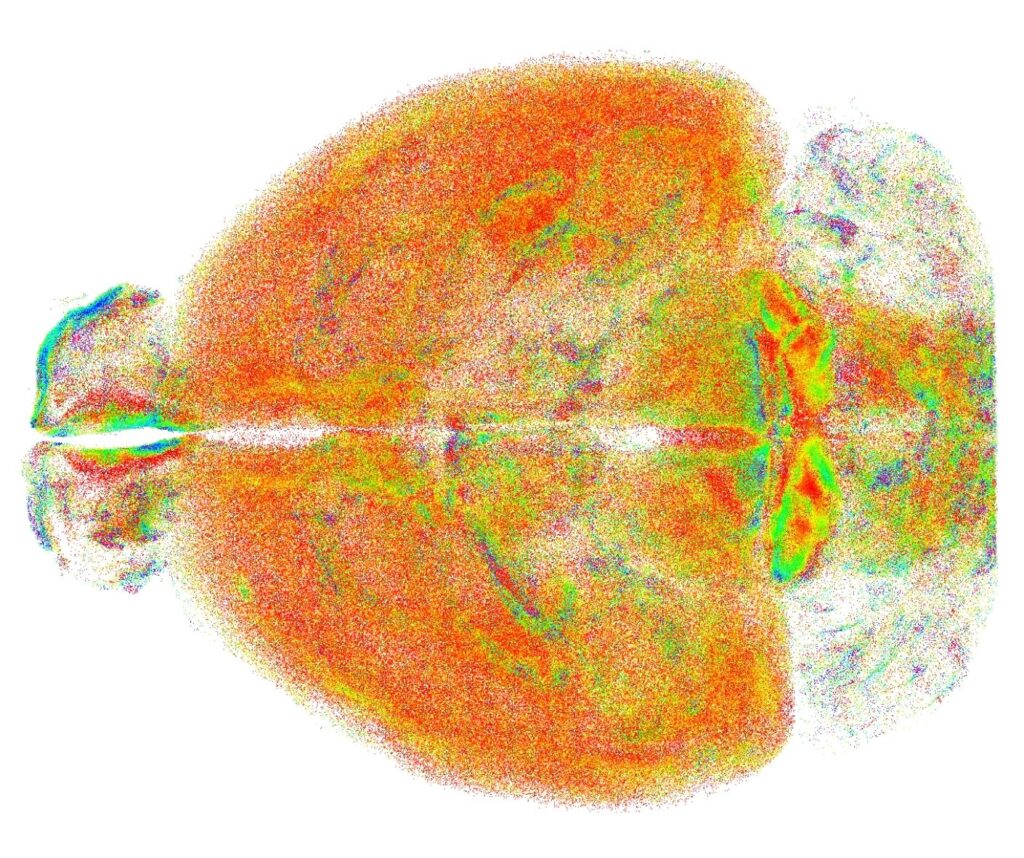

La nuova tecnica elaborata dai ricercatori, chiamata RAPID (acronimo di Rapid Autofocus via Pupil-split Image phase Detection) propone una nuova integrazione della microscopia a foglio di luce, capace di correggere in tempo reale i disallineamenti introdotti dal campione, consentendo di visualizzare e rappresentare interi cervelli di modelli murini con risoluzione subcellulare.

L'alta risoluzione garantita da RAPID – che è anche oggetto di un brevetto internazionale di cui sono titolari Unifi, Lens e Cnr - ha permesso ai ricercatori di studiare su scala dell'intero cervello problematiche finora analizzate solo in piccole aree circoscritte. Si è indagata, ad esempio, la distribuzione spaziale di un particolare tipo di neuroni – che esprimono somatostatina – mostrando come queste cellule tendono ad organizzarsi in cluster spaziali, che si sospetta rendano più efficace la loro azione inibitoria.

Un'altra applicazione riguarda la microglia, un insieme di cellule con diverse funzioni (dalla risposta ad elementi patogeni alla regolazione della plasticità dei neuroni), la cui forma cambia a seconda del ruolo che svolgono. L'analisi della microglia effettuata con RAPID ha evidenziato differenze significative tra varie regioni del cervello, aprendo la strada a nuovi studi sul ruolo di questa popolazione cellulare.